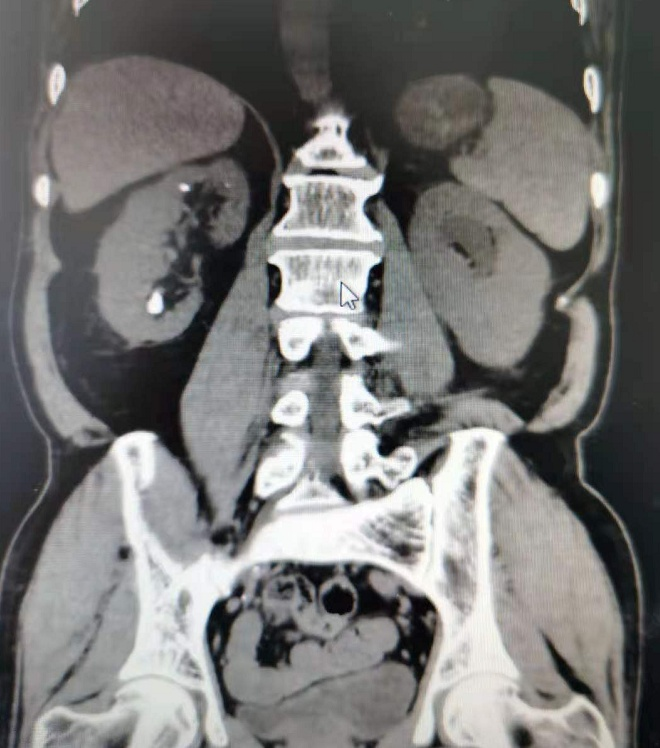

此例患者为男性,65岁,BMI:24.3kg/m2,主因“肾下盏结石”收住入院,结石位于肾下盏前组盏,结石大小约为1.2X1.5cm,CT值为1532HU,该病例入院后,经泌尿外科三病区主任包军胜、主任医师左陵君、副主任医师何綦琪综合考虑评估后,采用了新技术超微经皮肾镜碎石取石术(SMP)进行手术治疗。

术前CT平扫提示右肾下盏结石